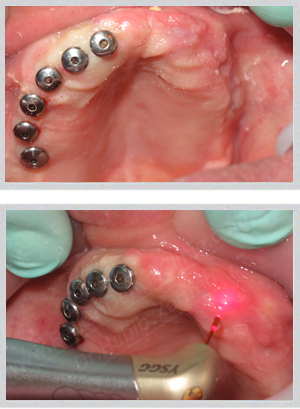

Fixed implant bridge replacing complete denture Beirut Lebanon

The gap between a removable denture and a fixed implant bridge is not a matter of aesthetics alone. Dentures accelerate bone resorption, create instability that worsens over time, and require adhesives that patients describe with consistent frustration. Fixed implant bridges load the bone directly — preserving it, stimulating it, and anchoring a restoration that does not move under any circumstance.